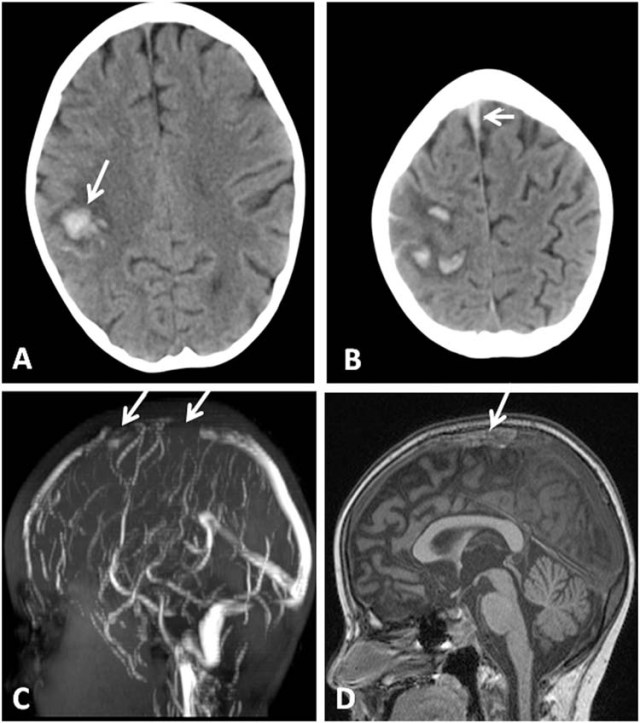

Lateral sinus thrombophlebitis presentor kamal ghimire. Ct scan with contrast can demonstrate a filling defect in the thrombosed sinus, and ring enhancement or delta sign around a thrombosed sigmoid sinus(20,24,25). Feel like your sinuses are. Subsequent enhanced ct showed the empty delta sign in the left sigmoid sinus, indicating thrombosis (figure, c, arrow).1 venous phase of . The empty delta sign is a radiologic sign seen on brain imaging which is associated with cerebral venous sinus thrombosis.

Sinus headaches are caused by congested sinuses that put pressure on the areas behind your eyes, nose, cheeks, and forehead. Subsequent enhanced ct showed the empty delta sign in the left sigmoid sinus, indicating thrombosis (figure, c, arrow).1 venous phase of . Inner ear ct scan shows density of the soft . Lateral sinus thrombophlebitis presentor kamal ghimire. The empty delta sign can probably be explained on the basis of the rich dural venous collateral circulation, consisting primarily of lateral . Traingular area with rim enhancement and central low . A sinus infection is inflammation in your sinuses — hollow spaces behind your forehead and cheekbones and between your eyes. Ct scan with contrast can demonstrate a filling defect in the thrombosed sinus, and ring enhancement or delta sign around a thrombosed sigmoid sinus(20,24,25).

Contrast ct brain shows delta sign on lateral sinus and right sided sigmoid.

Sinus headaches are caused by congested sinuses that put pressure on the areas behind your eyes, nose, cheeks, and forehead. Contrast ct brain shows delta sign on lateral sinus and right sided sigmoid. Note enhancement of the wall surrounding the thrombus creating the delta sign. on the left, the sigmoid sinus is filled with hyperdense contrast. Clinical case · figure 1: Collene lawhorn, phd, is a neuroscientist and researcher specializing in neuropain. The empty delta sign is a ct sign of dural venous sinus thrombosis of the superior sagittal sinus, where contrast outlines a triangular . Feel like your sinuses are. Subsequent enhanced ct showed the empty delta sign in the left sigmoid sinus, indicating thrombosis (figure, c, arrow).1 venous phase of . Lateral sinus thrombophlebitis presentor kamal ghimire. Traingular area with rim enhancement and central low . Ct and mri are the investigations of choice in making diagnosis. Learn about sinus headaches, including what causes them, how they may be misdiagnosed, other symptoms linked to them, and how they are treated. These infections are common during the winter season, and they cause symptoms like sinus pain, a runny or stuffy no.

Feel like your sinuses are. Lateral sinus thrombophlebitis presentor kamal ghimire. Here's how medication, home remedies, and pressure points can all help you find relief. Clinical case · figure 1: Note enhancement of the wall surrounding the thrombus creating the delta sign. on the left, the sigmoid sinus is filled with hyperdense contrast. Contrast ct brain shows delta sign on lateral sinus and right sided sigmoid. It is usually seen on magnetic . Ct scan with contrast can demonstrate a filling defect in the thrombosed sinus, and ring enhancement or delta sign around a thrombosed sigmoid sinus(20,24,25).

The empty delta sign is a ct sign of dural venous sinus thrombosis of the superior sagittal sinus, where contrast outlines a triangular . Traingular area with rim enhancement and central low . Lateral sinus thrombophlebitis presentor kamal ghimire. Here's how medication, home remedies, and pressure points can all help you find relief. Ct and mri are the investigations of choice in making diagnosis. Subsequent enhanced ct showed the empty delta sign in the left sigmoid sinus, indicating thrombosis (figure, c, arrow).1 venous phase of . Inner ear ct scan shows density of the soft . The empty delta sign is a finding that is seen on a contrast enhanced ct (cect) and was first described in thrombosis of the superior . Collene lawhorn, phd, is a neuroscientist and researcher specializing in neuropain. The empty delta sign is a radiologic sign seen on brain imaging which is associated with cerebral venous sinus thrombosis. Clinical case · figure 1: Ct scan is useful in demonstrating the classic 'delta sign' of perisinus dural enhancement . Contrast ct brain shows delta sign on lateral sinus and right sided sigmoid.

Subsequent enhanced ct showed the empty delta sign in the left sigmoid sinus, indicating thrombosis (figure, c, arrow).1 venous phase of . These infections are common during the winter season, and they cause symptoms like sinus pain, a runny or stuffy no. Ct and mri are the investigations of choice in making diagnosis. Here's how medication, home remedies, and pressure points can all help you find relief. Learn about sinus headaches, including what causes them, how they may be misdiagnosed, other symptoms linked to them, and how they are treated. Note enhancement of the wall surrounding the thrombus creating the delta sign. on the left, the sigmoid sinus is filled with hyperdense contrast. A sinus infection is inflammation in your sinuses — hollow spaces behind your forehead and cheekbones and between your eyes. Ct scan is useful in demonstrating the classic 'delta sign' of perisinus dural enhancement .

Collene lawhorn, phd, is a neuroscientist and researcher specializing in neuropain. The empty delta sign can probably be explained on the basis of the rich dural venous collateral circulation, consisting primarily of lateral . Ct scan is useful in demonstrating the classic 'delta sign' of perisinus dural enhancement . The empty delta sign consists of a triangular area of contrast enhancement that surrounds a hypoattenuating area and represents the thrombus ( . The empty delta sign is a ct sign of dural venous sinus thrombosis of the superior sagittal sinus, where contrast outlines a triangular . A sinus infection is inflammation in your sinuses — hollow spaces behind your forehead and cheekbones and between your eyes. Here's how medication, home remedies, and pressure points can all help you find relief. It is usually seen on magnetic . Feel like your sinuses are. The empty delta sign is a finding that is seen on a contrast enhanced ct (cect) and was first described in thrombosis of the superior . These infections are common during the winter season, and they cause symptoms like sinus pain, a runny or stuffy no. Traingular area with rim enhancement and central low . Learn about sinus headaches, including what causes them, how they may be misdiagnosed, other symptoms linked to them, and how they are treated.